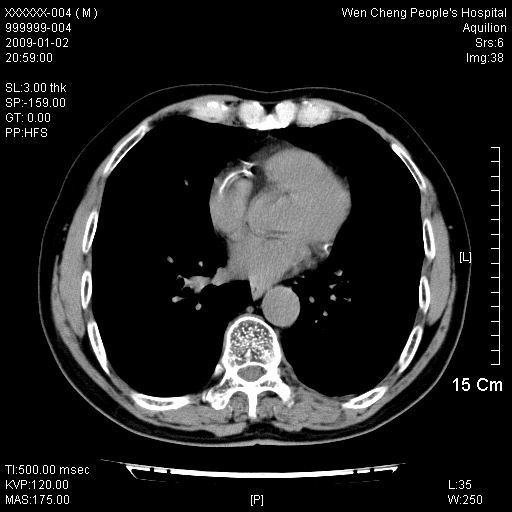

男性,73岁,有慢支病史,肿瘤系列标志物检验正常,血沉及血常规正常

右肺下叶背段小片状 磨玻璃样模糊影,内见血管及含气支气管像,支气管管壁增厚。考虑:慢性炎症!

1)不排除右肺下叶周围型肺癌可能;建议追踪复查。2)左右冠状动脉钙化。

右肺下叶背段小片状 实性与磨玻璃样影,内见血管及含气支气管像,支气管管壁增厚,边缘见长毛刺影。考虑:慢性炎症或肿瘤!建议抗炎治疗复查,密切观察随访!

右肺下叶片团状影内见扩张的含气支气管和支气管管壁增厚,其周有磨玻璃样模糊影和长毛刺。考虑慢性炎症可能性大。

2、右肺下叶片团状影内见扩张的含气支气管和支气管管壁增厚,其周有磨玻璃样模糊影和长毛刺。考虑周围型肺ca可能,结核不排。

高度提示细支气管肺泡癌,建议抗炎治疗半月观察病灶变化,如无明显改变,建议立即手术治疗.

病变形态非常不好呀,临床上血常规及症状也不明显,不太支持炎性病灶,高度警惕肿瘤病变,最好做个纤支镜检查。